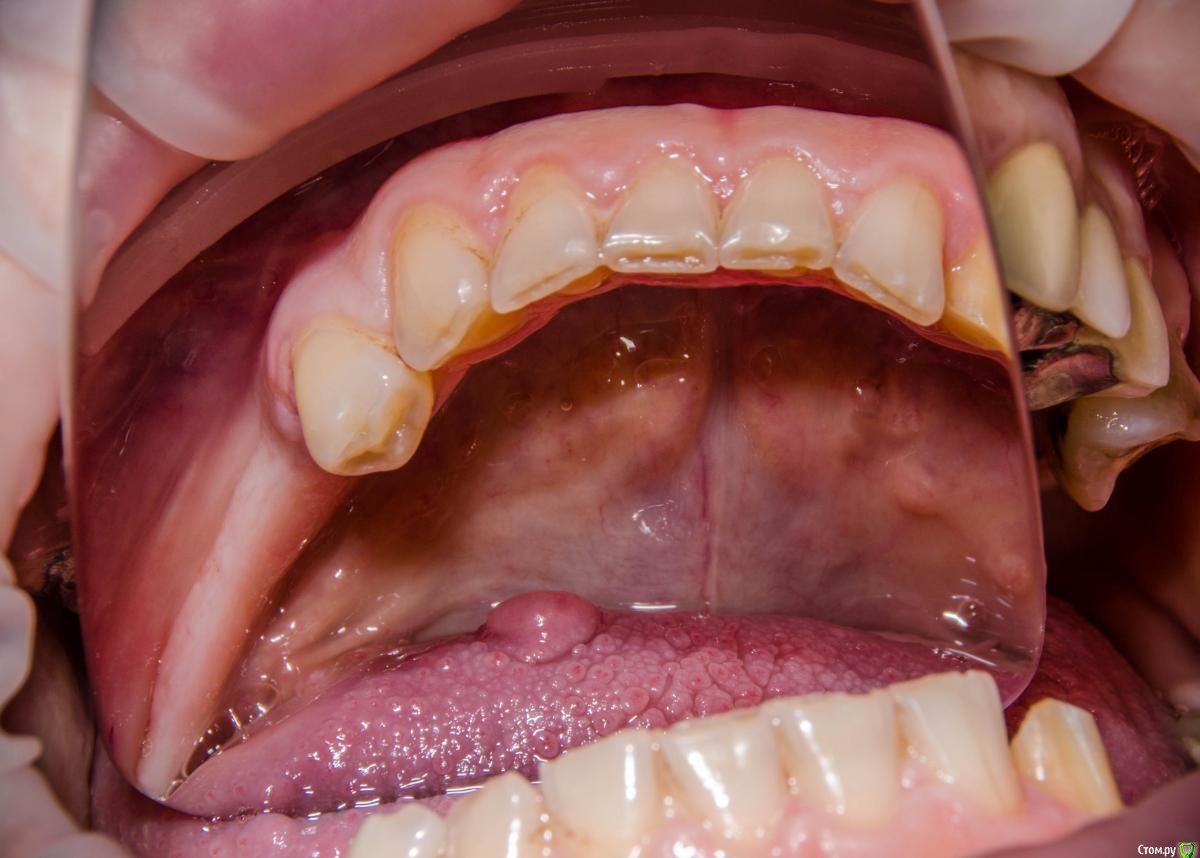

kamranchick Опубликовано 8 февраля, 2017 Автор Поделиться Опубликовано 8 февраля, 2017 когда до языка доберетесь?у нее 8 лет уже такая штучка, не растет и не мешает. а так, я думаю либо получать доступ как в Фрагискосе написано, либо коагулятором Ссылка на комментарий